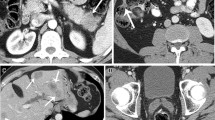

Second, some genetic alternations found in PDA have prognostic implications and may therefore serve as biomarkers. Blackford et al. [59] analyzed sequence data on 39 genes frequently mutated in PDA in a well-characterized series of 90 tumors and correlated the results with patient outcome. They found that loss of SMAD4 in a pancreatic cancer was associated with a shorter overall survival (11.5 months compared with 14.2 months in patients whose tumors had intact SMAD4). Taking these findings one step further, Iacobuzio-Donahue et al. [60] showed that PDAs with inactivated SMAD4 are more likely to metastasize widely than are PDAs with intact SMAD4. Taken together, these findings suggest that SMAD4 status could guide therapeutic approaches in patients with borderline resectable PDA. Patients with tumors that have SMAD4 inactivation may benefit from systemic therapy, as their tumors are more likely to be metastatic (Fig. 1b).

Examples of how genetic biomarkers may contribute to histologic diagnosis and/or clinical outcome prediction. a A colloid adenocarcinoma (hematoxylin and eosin stain; original magnification ×10). These tumors are strongly associated with GNAS codon 201 mutations and an improved outcome compared with tubular ductal adenocarcinomas, which are almost always GNAS wild-type tumors. b A pancreatic ductal adenocarcinoma with loss of SMAD4 (Immunostain for Smad4; original magnification ×40) as often mediated through a somatic mutation. This genetic alteration is usually associated with a particularly poor outcome with rapid widespread metastatic disease

Previous studies have shown that IPMNs harbor specific genetic alterations, including copy number changes [80] and intragenic mutations [81]. Recent comprehensive sequencing studies have shown that IPMNs harbor an average of 26 nonsynonymous coding mutations, with KRAS as the most frequently mutated gene (approximately 80 %) [8, 9, 82]. Although KRAS is also a hallmark of PDA, two other genetic alterations are highly prevalent in IPMNs (Table 1). In contrast to “common” PDAs (arising in the absence of an associated IPMN), GNAS codon 201 mutations are present in two thirds of IPMNs and inactivating RNF43 mutations can also be seen [82, 83]. Somatic mutations in GNAS lead to an activation of an alpha subunit of a G protein causing increased adenyl cyclase activity and high cyclic AMP production. GNAS mutations appear to be most prevalent in intestinal-type IPMNs and their associated invasive colloid adenocarcinomas [84]. Patients with colloid cancers usually have a more favorable outcome compared with those with a tubular PDA (Fig. 1a). Inactivating mutations in the tumor suppressor gene RNF43 are also found in a subset of IPMNs. The associated protein, a ubiquitin E3 ligase, has been implicated as an inhibitor of Wnt signaling [8]. The four most frequently involved genes in PDA play a role in IPMNs too. As mentioned, somatic KRAS mutations occur in a high proportion of IPMNs, with higher incidence in gastric and pancreatobiliary subtypes and the associated tubular adenocarcinomas [85–88]. Somatic TP53 mutations are almost exclusively found in areas of high-grade dysplasia or invasion, which indicates that this mutation is a relatively late event in carcinogenesis [88–91]. Most noninvasive IPMNs show intact expression of the tumor suppressor gene SMAD4, whereas SMAD4 loss can be seen in invasive carcinomas arising in association with IPMNs, again suggesting that SMAD4 is targeted late in neoplastic progression [92, 93]. Similarly, loss of p16 is very common in invasive carcinoma arising in association with an IPMN, whereas p16 is preserved in most lower-grade IPMNs [93]. Other mutations that can be found in IPMNs include mutations of PIK3CA (approximately 10 %) [88], STK11 (also known as LKB1) (5 % of sporadic IPMNs) [94] and BRAF (2.7 % of IPMNs) [95, 96].